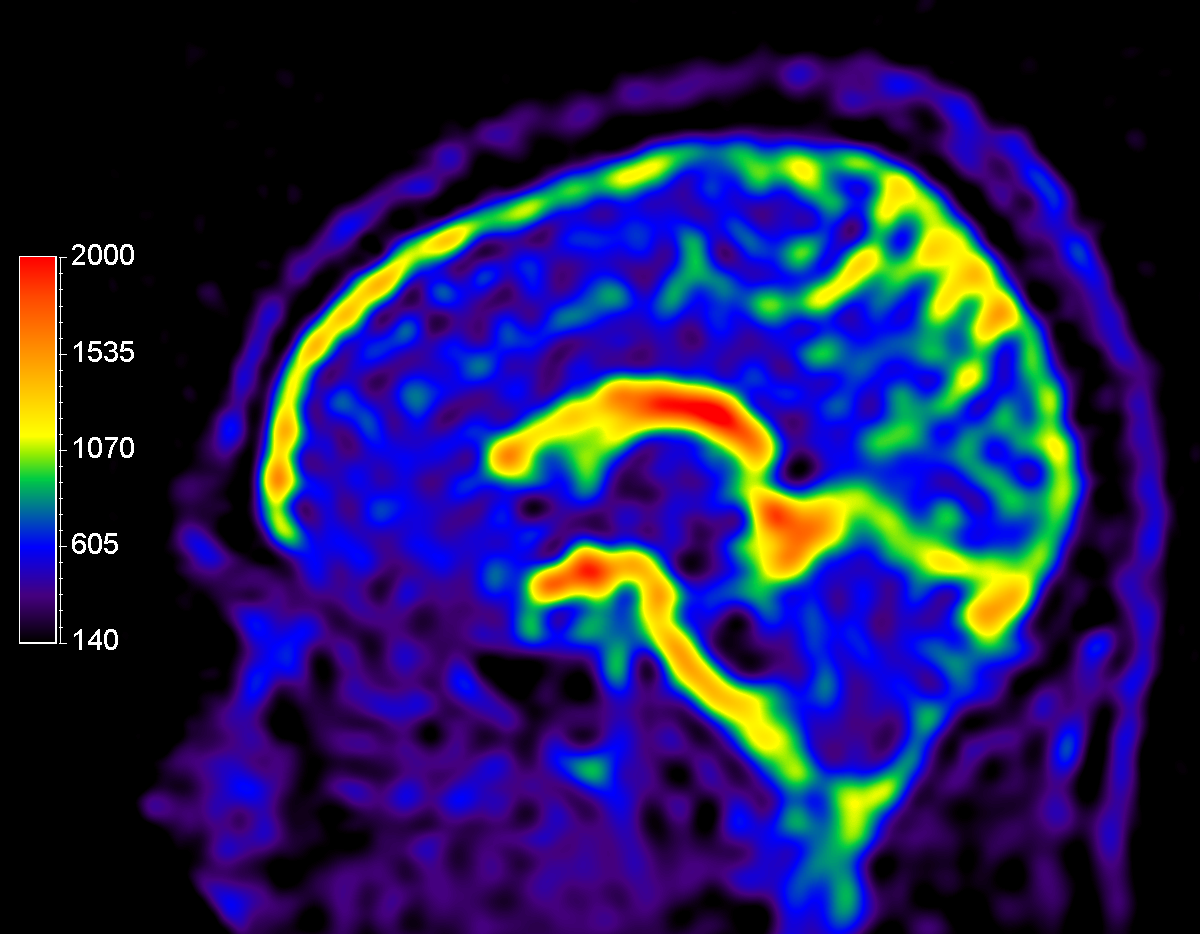

Sagittal 23Na bFFE

Multi Nuclei - Brain imaging (23Na)

Make multi-nuclei imaging and spectroscopy become part of your clinical operations via a seamless integrated workflow for multi-nuclei image acquisition, spectroscopy, reconstruction, and viewing. The nucleus is just a scan parameter like any other sequence parameter. A single ExamCard can be used to run both proton and non-proton imaging. Reconstruction and viewing of non-proton images or spectra, as well as the process for sending the data to PACS is fully integrated, so workflow does not differ from proton imaging. The dual tuned head coil from Rapid biomedical is immediately recognized by the ExamCard interface and your full brain exam, including acquisition of proton and other nuclei, can be completed without switching coils.